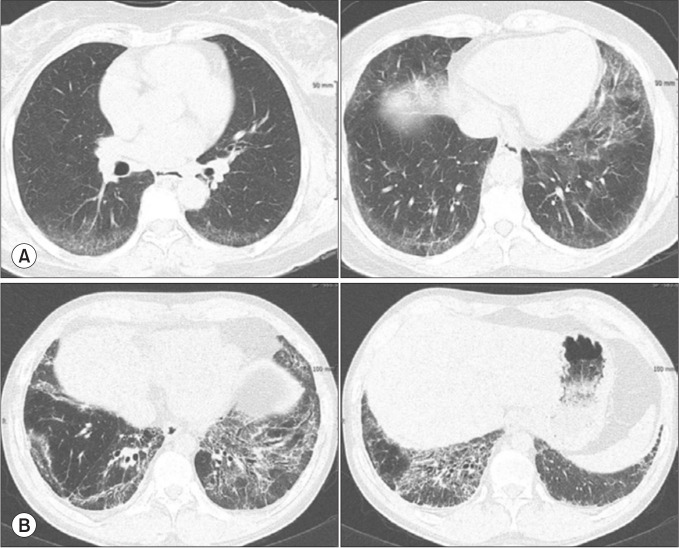

Idiopathic nonspecific interstitial pneumonia (iNSIP) is recognized as a distinct entity among various types of idiopathic interstitial pneumonias. It is identified histologically by the nonspecific interstitial pneumonia pattern. A diagnosis of iNSIP is feasible once secondary causes or underlying diseases are ruled out. Usually presenting with respiratory symptoms such as shortness of breath and cough, iNSIP has a subacute or chronic course. It predominantly affects females aged 50 to 60 years who are non-smokers. Key imaging findings on chest high-resolution computed tomography include bilateral reticular opacities in lower lungs, traction bronchiectasis, reduced lung volumes and, ground-glass opacities. Abnormalities are typically diffuse across both lungs with subpleural distributions. Treatment often involves systemic steroids, either alone or in combination with other immunosuppressants, although evidence supporting effectiveness of these treatments is limited. Prognosis is generally more favorable for iNSIP than for idiopathic pulmonary fibrosis, with many studies reporting a 5-year survival rate above 70%. Antifibrotic agents should be considered in a condition, termed progressive pulmonary fibrosis, where pulmonary fibrosis progressively worsens.